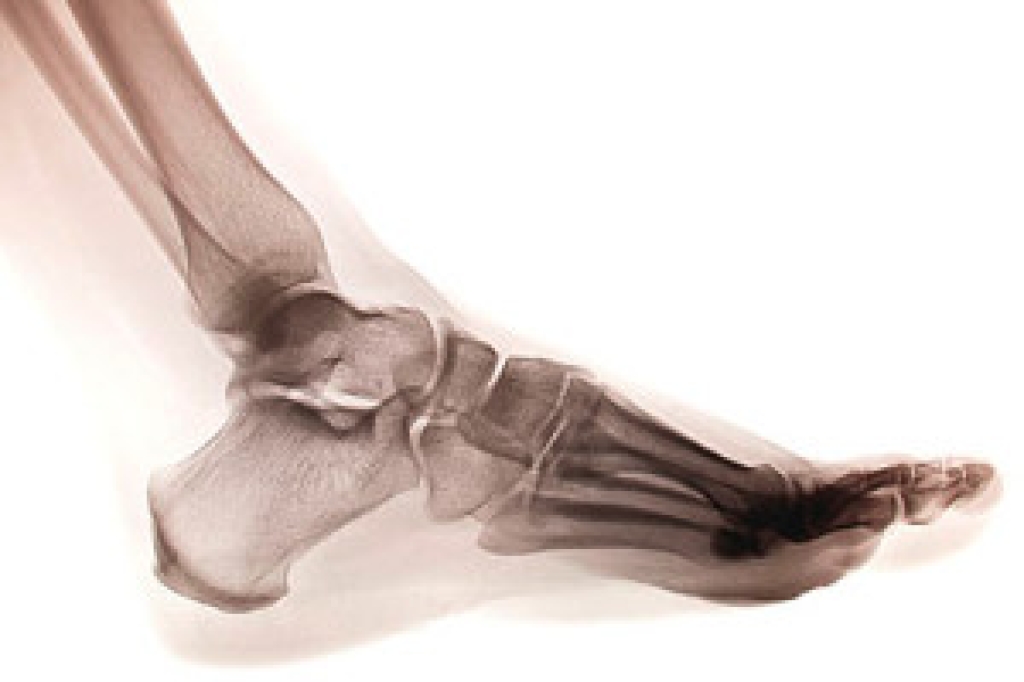

Podiatric biomechanics is a particular sector of specialty podiatry with licensed practitioners who are trained to diagnose and treat conditions affecting the foot, ankle and lower leg. Biomechanics deals with the forces that act against the body, causing an interference with the biological structures. It focuses on the movement of the ankle, the foot and the forces that interact with them.